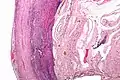

Pathology

Even for clinically certain appendicitis, routine histopathology examination of appendectomy specimens is of value for identifying unsuspected pathologies requiring further postoperative management.[61] Notably, appendix cancer is found incidentally in about 1% of appendectomy specimens.[62]

Pathology diagnosis of appendicitis can be made by detecting a neutrophilic infiltrate of the muscularis propria.

Periappendicitis (inflammation of tissues around the appendix) is often found in conjunction with other abdominal pathology.[63]

Micrograph of appendicitis and periappendicitis. H&E stain

Micrograph of appendicitis showing neutrophils in the muscularis propria. H&E stain

Acute suppurative appendicitis with perforation (at right). H&E stain